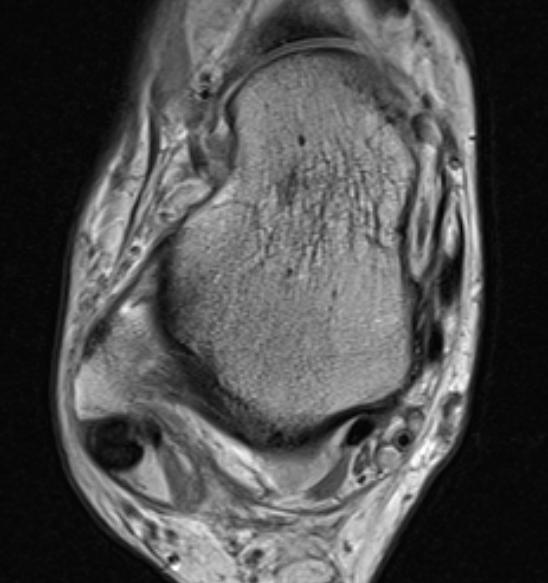

MRI

ATFL normal

Torn ATFL

CFL

PTFL

Deltoid ligament